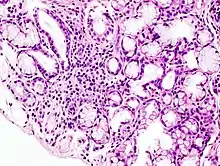

Transverse section of Villus showing goblet cells

The villi are covered with goblet cells. About a quarter to a half of the villi cells are mucous producing.

The pancreas is a large endocrine and exocrine gland situated retroperitonealy beneath the stomach. The endocrine portion of the gland secretes Insulin and glucagon from the Islets of Langerhans (see thumbnail of histology). This function of the pancreas will be looked at else where. The microscopic structure of the pancras is similar to the salivary glands, the acini secrete enzymes, and the ductules and ducts secrete large quantities of a bicarbonate rich juice. These travel down the pancreatic duct to the second part of the duodenum where it exits via the Ampulla of Vater, protected by the Sphincter of Oddi.